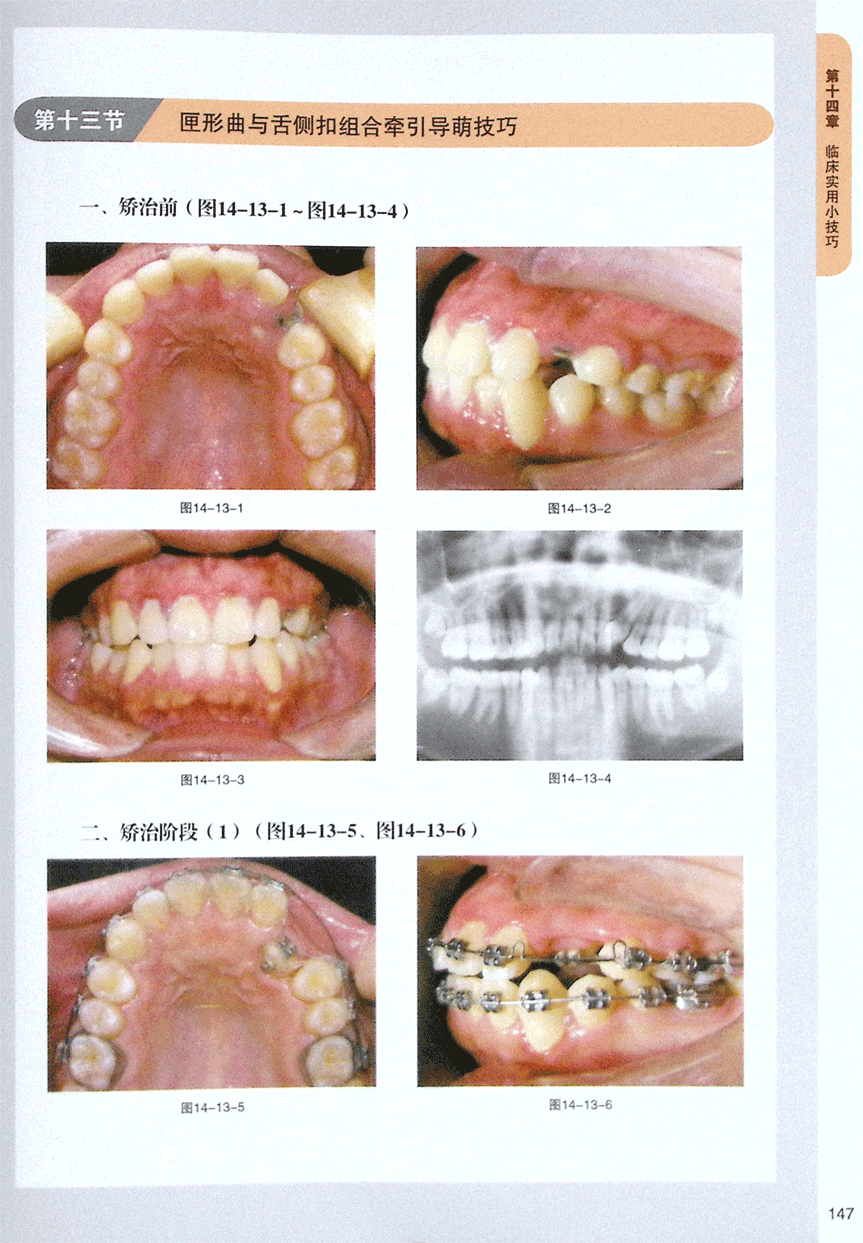

第十三节 匣形曲与舌侧扣组合牵引导萌技巧